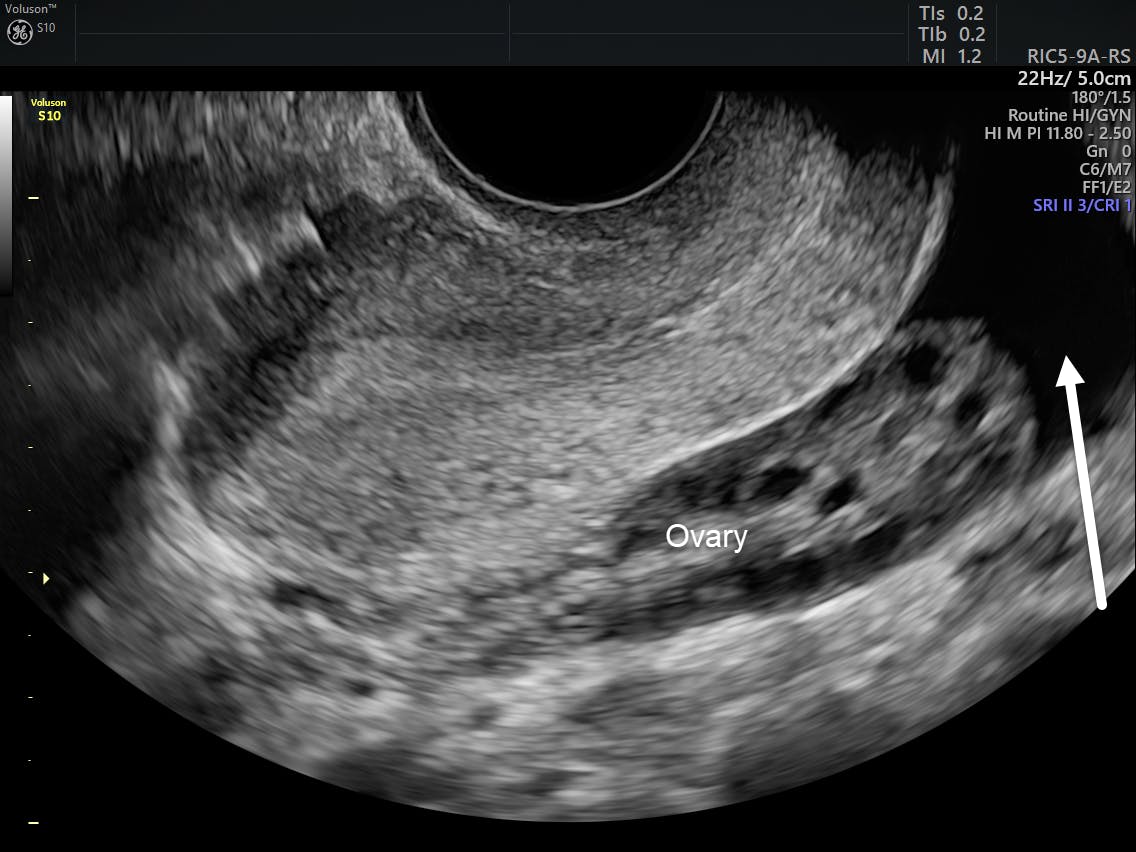

Polyp a tumor whose origin is the endometrium. At this time you can already see the dominant follicle. In thin patients relatively small volume of fluid can be found. Physiological ff is detected mostly during ovulation and a few days after ovulation in 36 40 of non pregnant women according to previous studies 8 11.

During the menopausal period this finding arouses suspicion of malignancy. As the follicle matures more fluid is released and accumulates into its center. Therefore outside of their ovulation period these women would not be likely to have sonographically detectable amounts of physiological ff. Clear fluid without internal echoes is likely to be reactive.